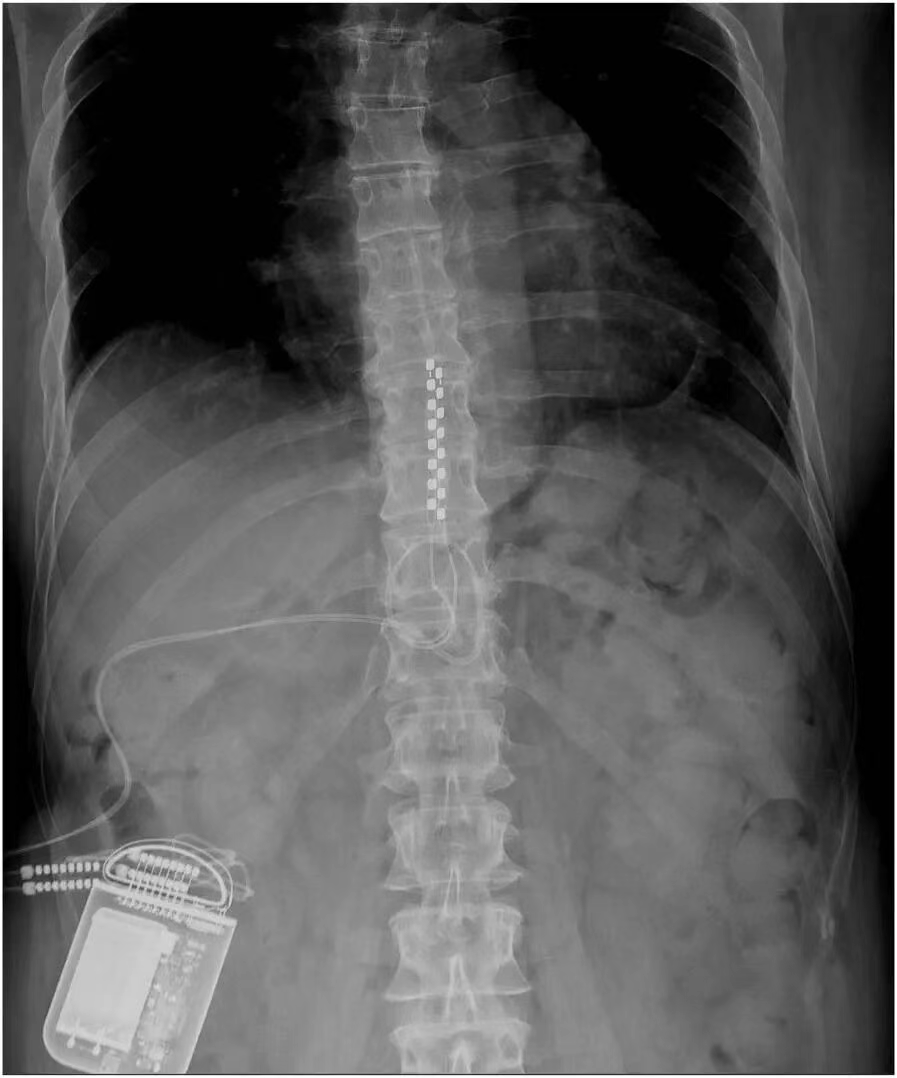

如果患者在试验期内对脊髓电刺激反应良好,且医生认为长期治疗可能对患者有益,那么就会考虑进行永久植入手术。在手术前,医生会与患者充分沟通,讨论植入的具体方式、预期的治疗效果以及可能存在的风险等。手术过程中,患者通常会接受全身麻醉或局部麻醉,医生会在透视引导下,将永久性电极精准地植入到硬膜外间隙,并确保电极与脊髓的位置关系合适。电极植入后,会将其与植入式脉冲发生器(IPG)相连,IPG 通常会被放置在患者的腹部或臀部皮下。手术后,医生会对 IPG 进行编程,根据患者的个体情况设置合适的刺激参数,以达到最佳的治疗效果。